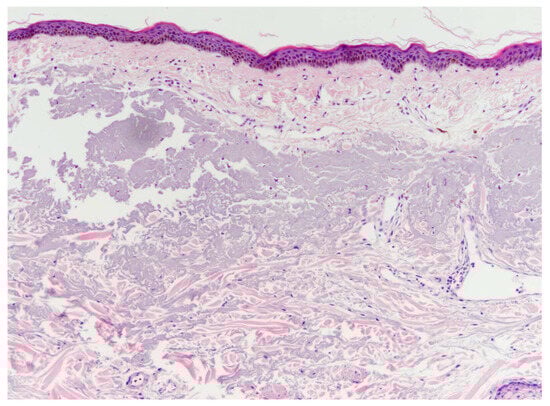

4.3. Cadaver Study